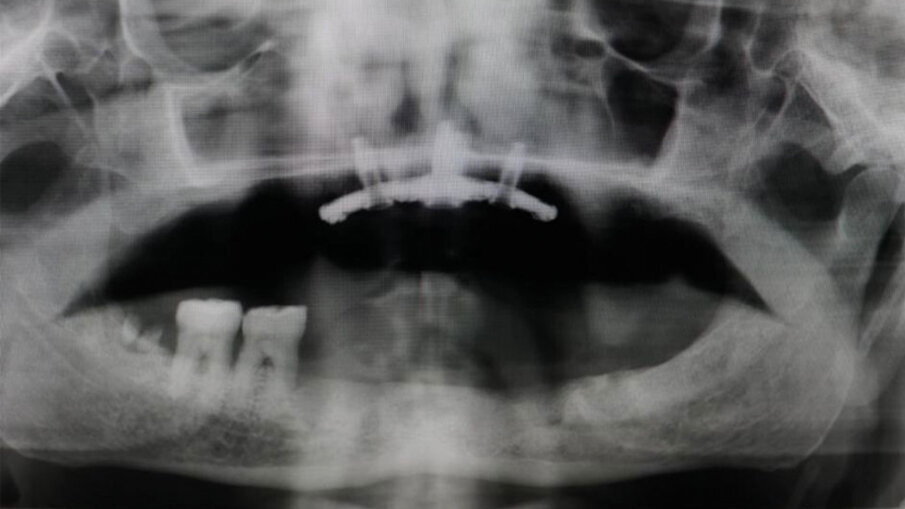

Fig. 3 - RX iniziale. Il Paziente ottantenne si presenta con una protesi mobile realizzata e inserita da oltre 20 anni. Il desiderio di avere i denti fissi non l’ha mai abbandonato. Dalla RX si evince la chiara assenza totale di osso, situazione che non permette l’inserimento degli impianti in titanio tramite intervento tradizionale. Questo caso è stato affrontato tramite l’inserimento del Premaxillary Device.

Fig. 7 - RX dopo l’inserimento del Premaxillary Device.

Fig. 10 - RX dopo 3 Mesi. Si è proceduto con l’inserimento dei monconi più provvisorio fisso.